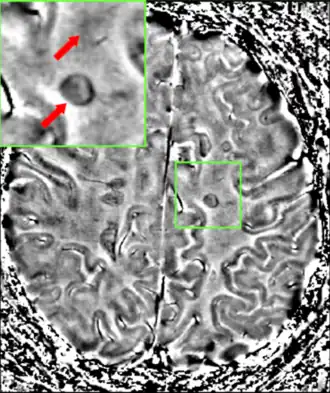

Central vein signs (CVSs) have been proposed as a good indicator of MS in comparison with other conditions causing white lesions.[96][97][98][99] One small study found fewer CVSs in older and hypertensive people.[100] Further research on CVS as a biomarker for MS is ongoing.[101]

In vivo vs postmortem lesion visibility in MRI scans

Only postmortem MRI allows visualization of sub-millimetric lesions in cortical layers and in the cerebellar cortex.[102]